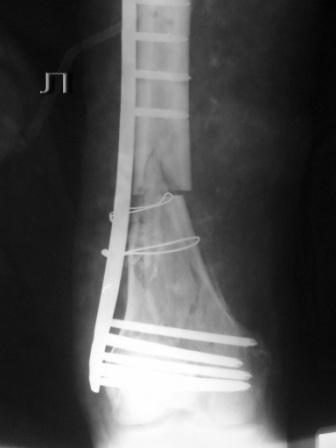

Оставлен клинически значимый варус, видно градусов 8-10. Для уточнения можно сделать снимок симметричного сегмента и скиаграммы наложить.

Не стоило открывать промежуточные отломки и вязать их проволокой. Это ухудшает их кровоснабжение и может привести к несращению. Не во все случаях, конечно. Удачи.

Сложность репозиции привела к "освобождению" промежуточных отломков - появился значительный костный дефект - пришлось создавать картинку + добавили коллапан.

Не удивляйтесь, если пластина сломается(((

Какова возможная причина перелома импланта, ведь принцып "мостовидности" пластины LCP соблюден!?

"Мостовидность" вовсе не подразумевает только LCP, также как и LCP не озачает обязательную "мостовидность".

Мостовидность это только часть , так называемого, биологического принципа.Биологический принцип предполагает баланс между механическими свойствами остеосинтеза и сохранением кровоснабжения кости и окружающих мякких тканей. Мостовидная фиксация обеспечивает относительную, эластичную стабильность, которая при малоинвазивной технике (MIPO), т.е, при закрытой репозиции и нескелетировании кости дает хороший шанс на быстрое течение репаративных процессов и сращение перелома.

В Вашем примере, как мне кажется, была довольно травматичная открытая реползиция со скелетированием концов перелома. В результате отсутствует необходимая биологическая составляющая для нормальной репарации кости. кроме того, положение отломков по оси - так себе, и имеется значимый медиалный дефект. Так что к био-логической мостовидной технике фиксации переломов этот случай не имеет никакого отношения. Увы(